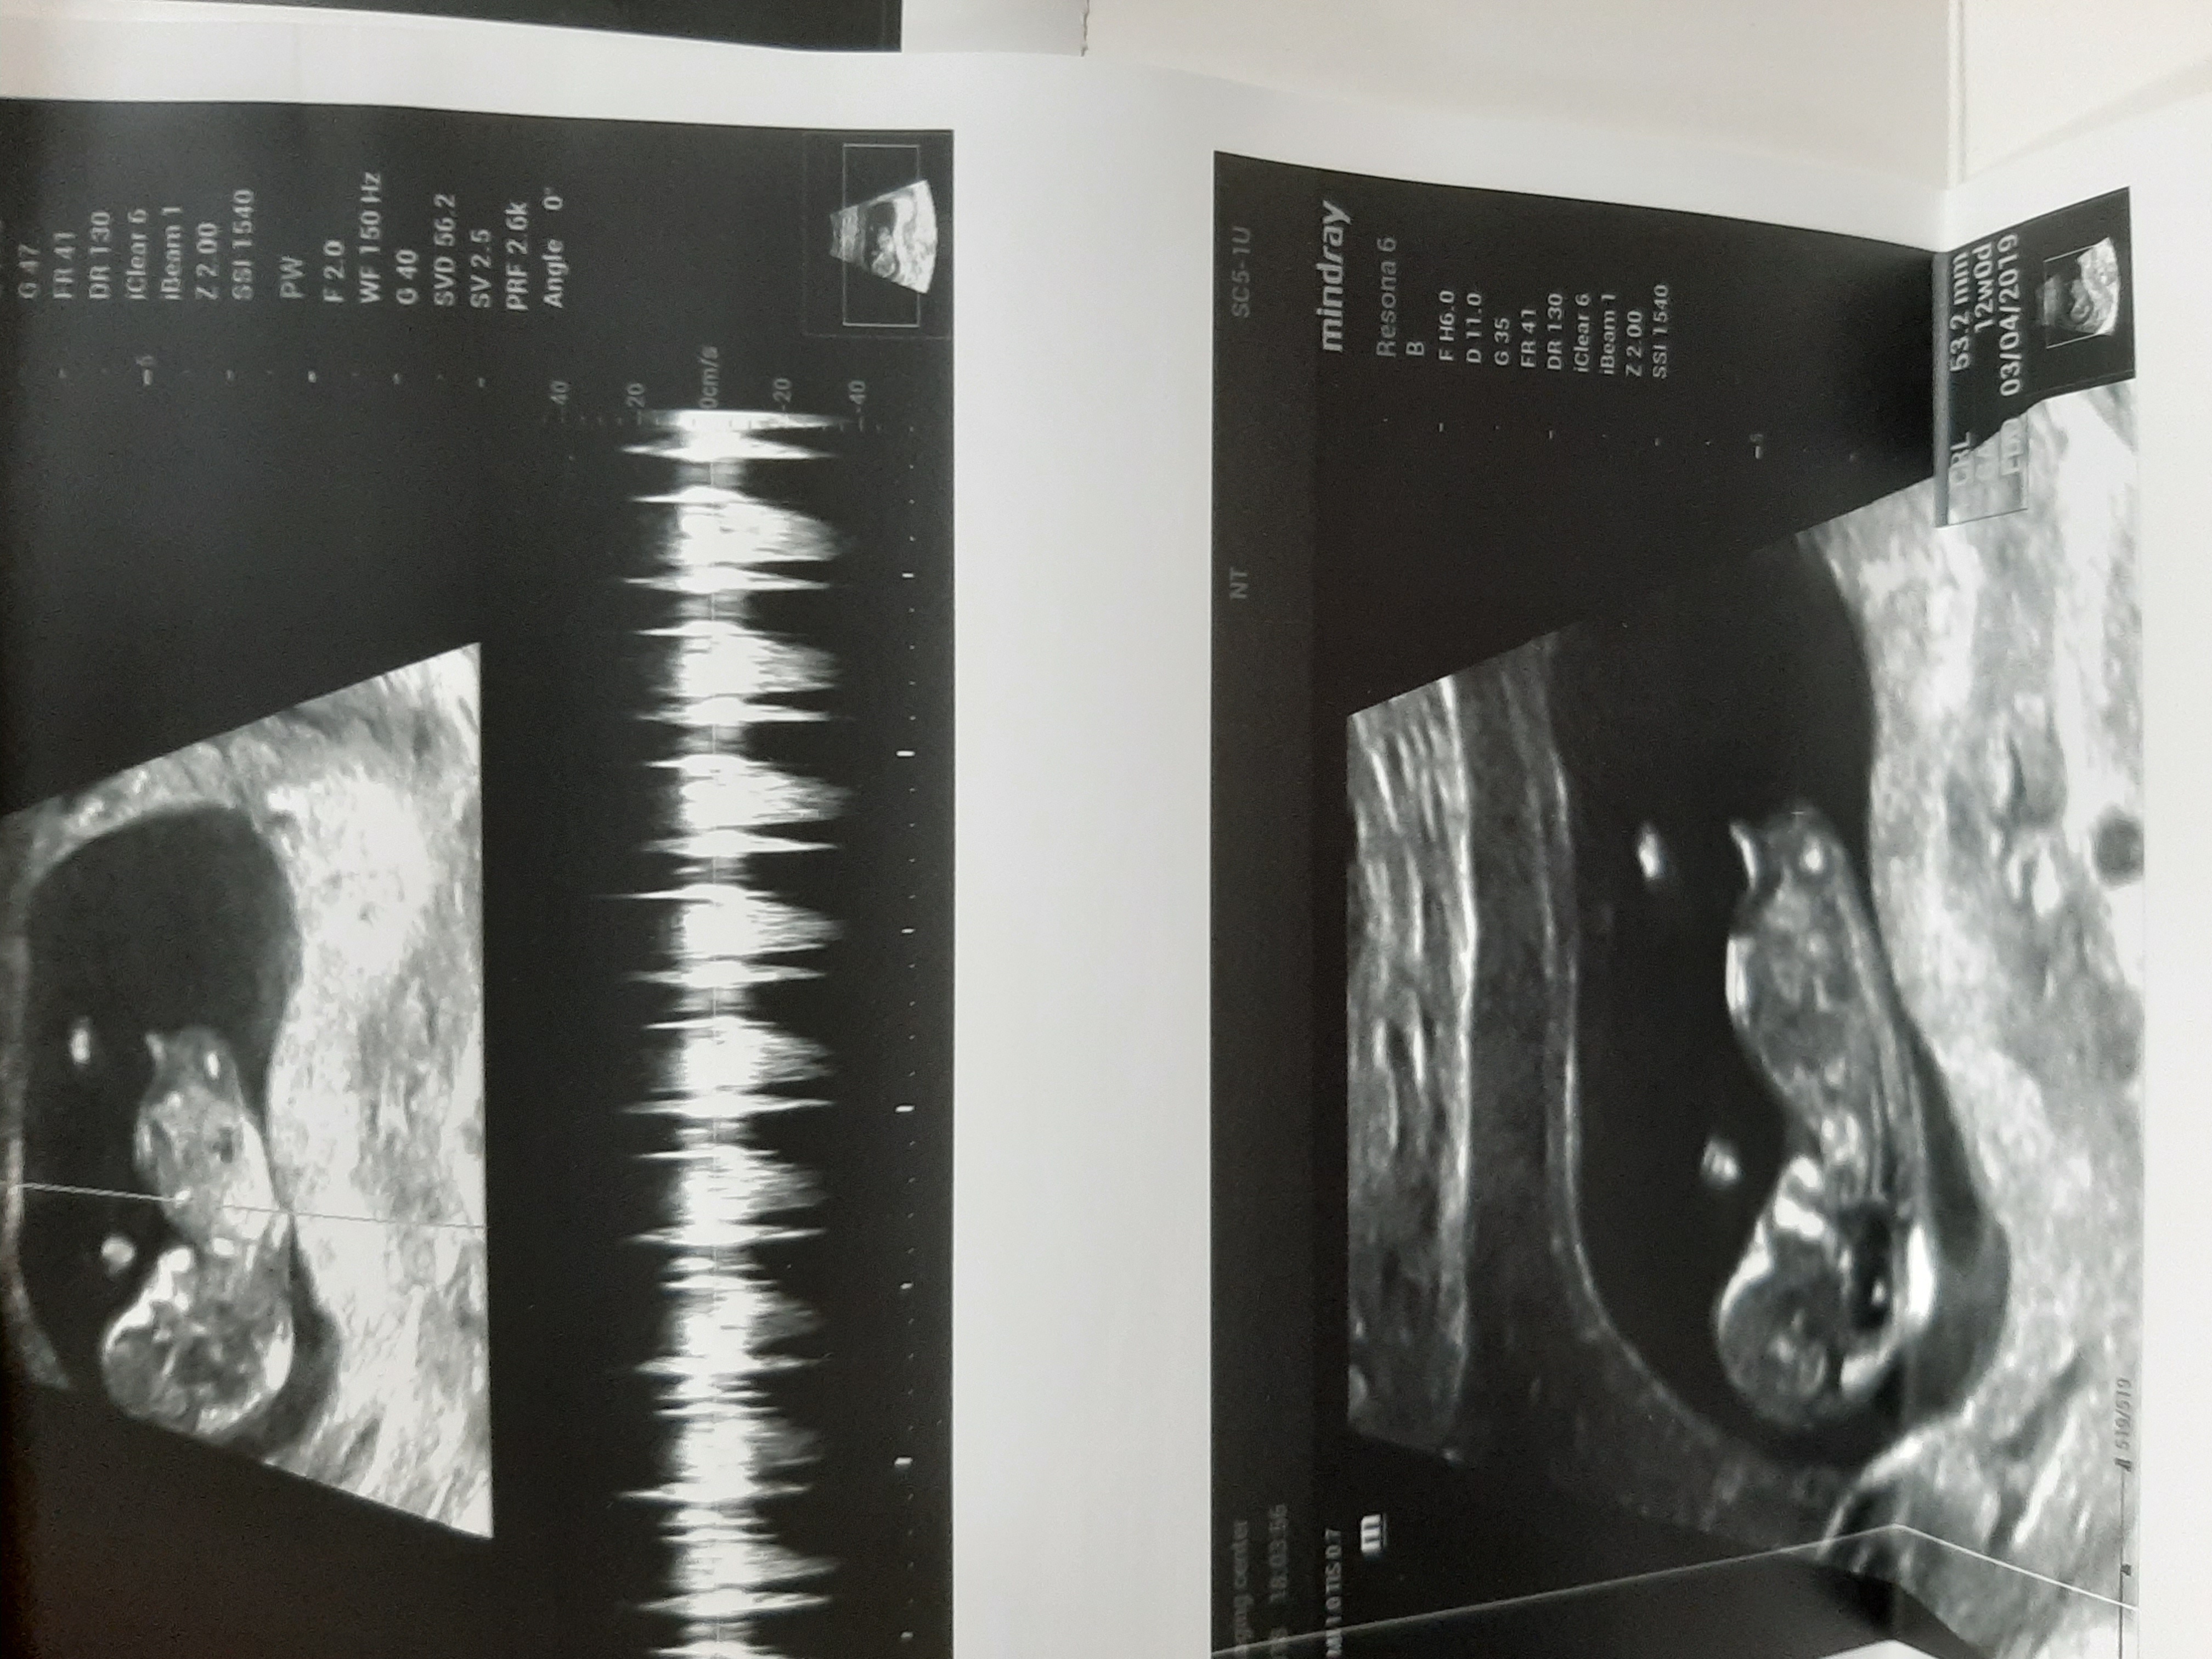

انتهاشو نگا کنی اگه روبه بالاباشه پسره اگه به پایین باشه یا چسبیده باشه دختره الان عکس ان تی دختروپسرمو میزارم ببین تفاوتشونو